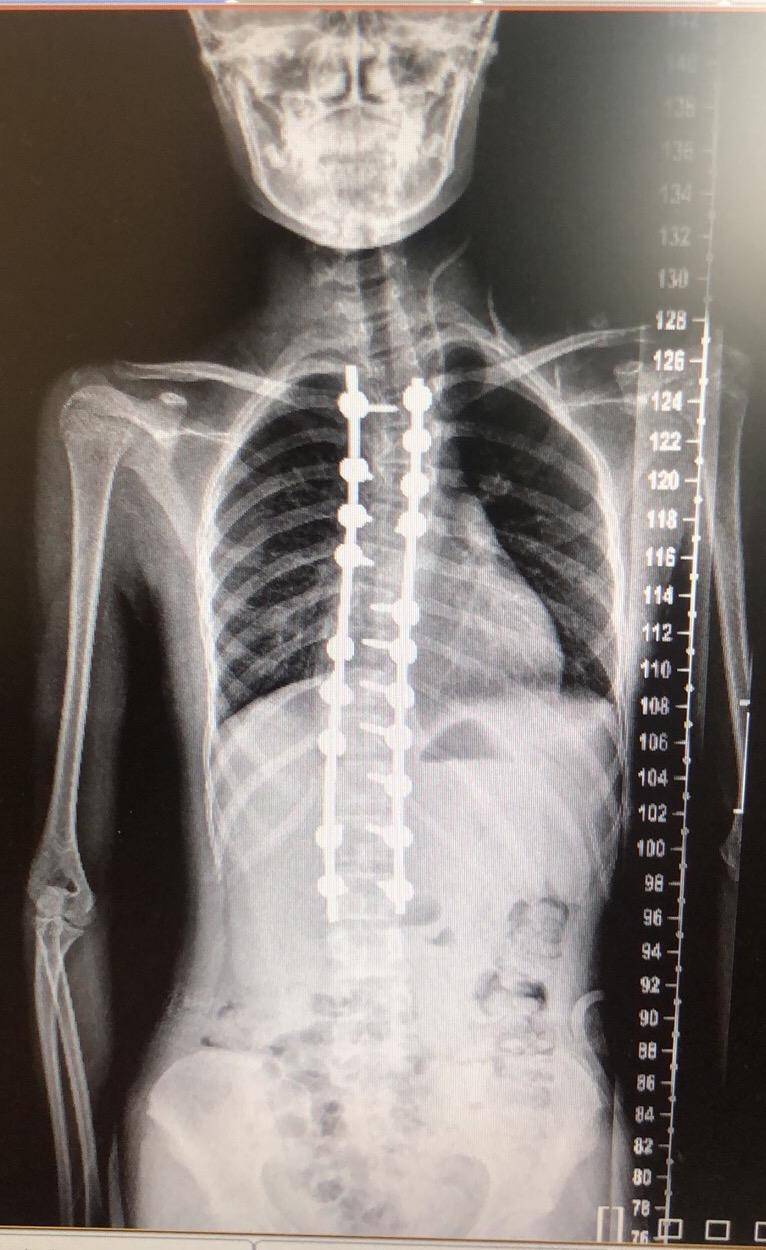

脊柱侧弯矫正3个月剃刀背14度减至0度73